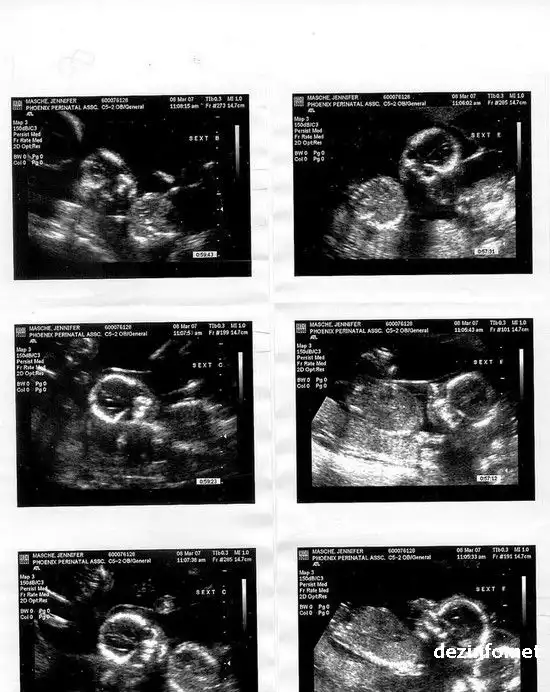

Мама еще беременна: